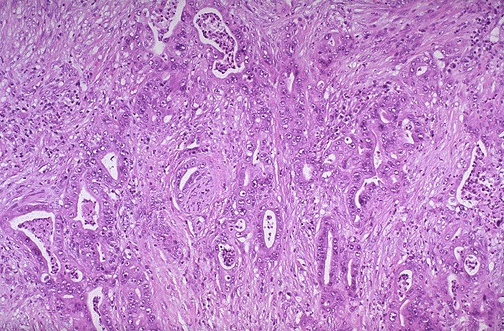

| The appearance of an adenocarcinoma of the pancreas is seen at medium magnification. Just to the left of center can be seen perineural invasion by the neoplasm, which is composed of very irregular glands. Involvement of the nerves can lead to the intense, constant pain typical for infiltrative malignant neoplasms. |